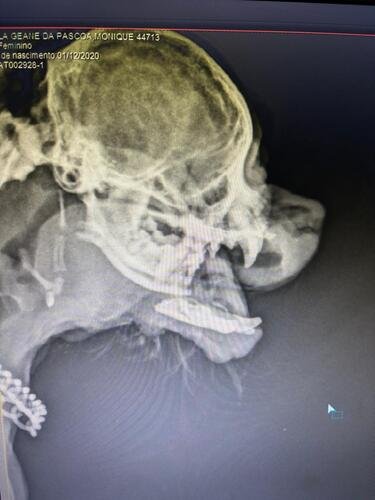

Horas depois, finalmente nos contaram que ela estava estabilizada, mas nos explicaram o quadro clínico: Monique havia quebrado a mandíbula em dois lados diferentes do rosto. A fratura fez com que o centro da mandíbula ficasse basicamente pendurado. O osso quebrado acabou cortando a carne, gerando uma fratura exposta que causou a hemorragia.

Ela está estabilizada, mas precisa de duas cirurgias urgentes para se recuperar:

Uma osteossíntese com placa e pino para reconstruir a mandíbula.

Segue as fotos dela e o raio-x: